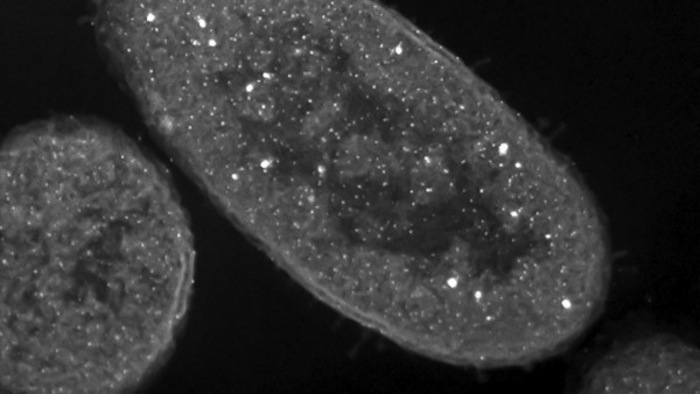

Para el estudio, cepas de Pseudomonas aeruginosa fueron matadas con una solución de nitrato de plata, un agente antibacteriano común. Después de esto, los cadáveres bacterianos se aislaron, limpiaron y fueron expuestos a cepas de Pseudomonas “frescas” y vivas.

Lo que no se conocía era el “efecto zombie” ocasionado por la plata. Por lo que tuvieron que matar primero a una muestra de la bacteria Pseudomonas aeruginosa para descubrir este mecanismo macabro. Después de esto, cuando se expusieron bacterias a aquellas que ya habían muerto por el nitrato de plata, los científicos fueron testigos de una masacre microscópica en la que hasta el 99.99 por ciento de las bacterias que antes estaban con vida encontraron su perdición.